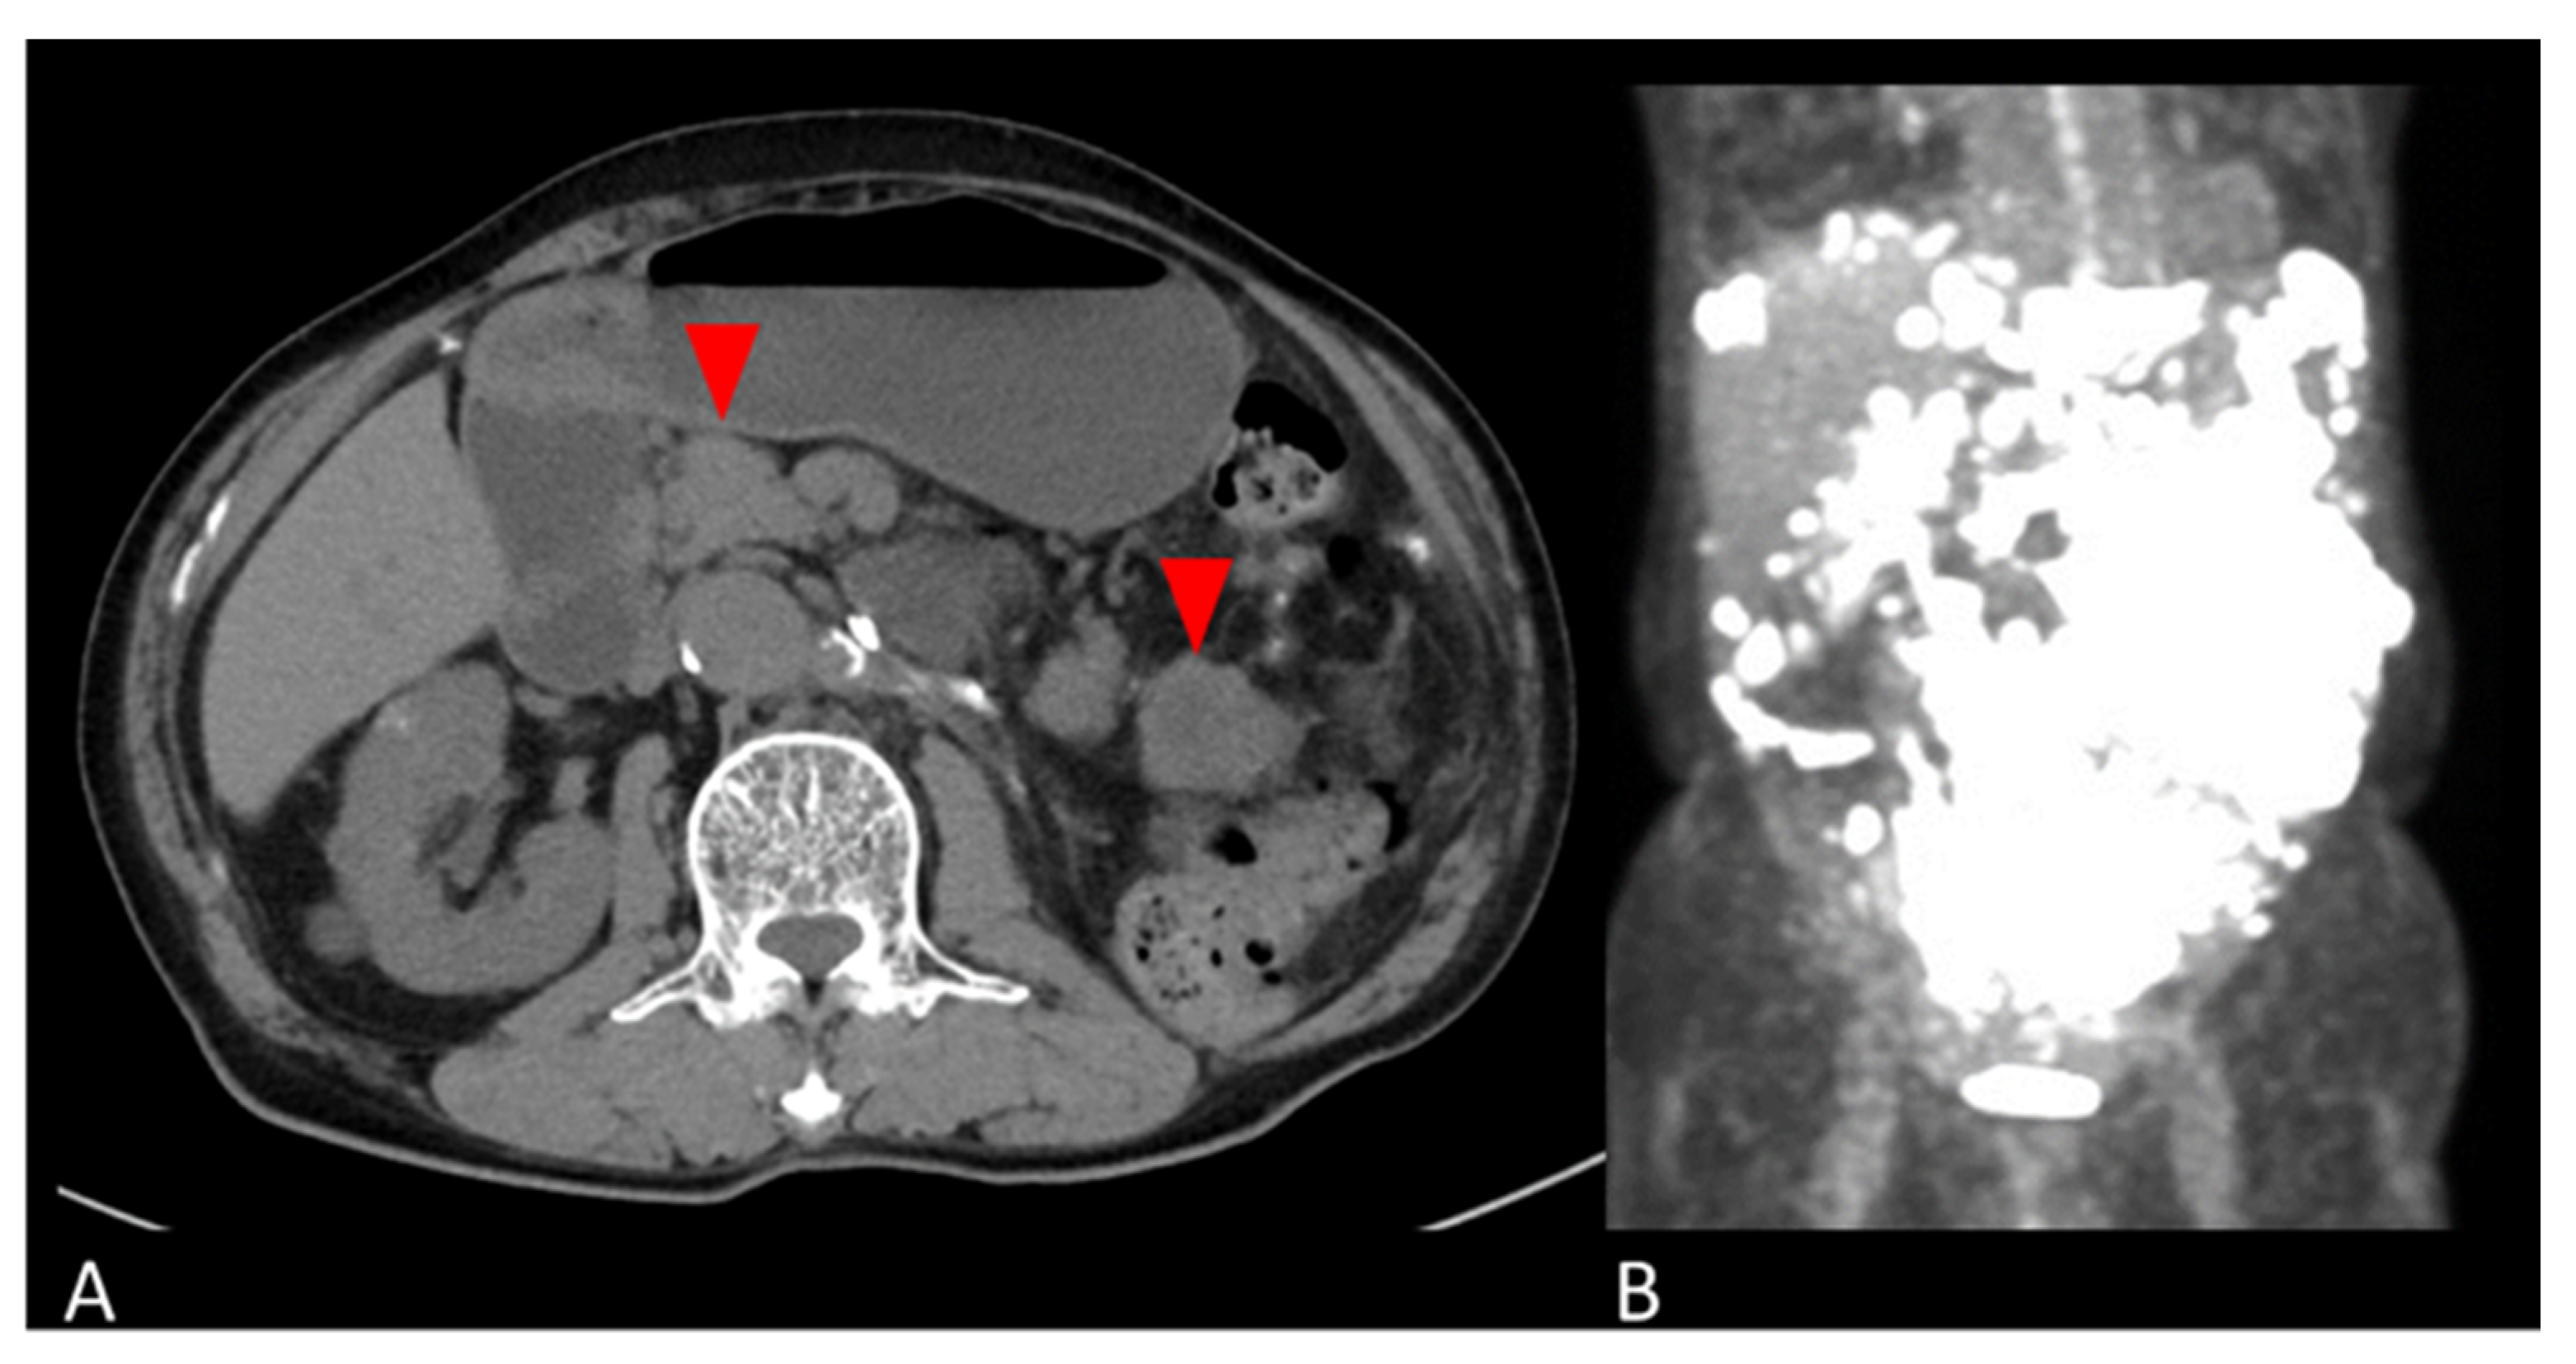

2. Case Presentation

2.1. Clinical Summary

2.2.2. Retroperitoneal Tumor Specimen